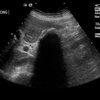

A

Wall-Echo-Shadow Triad

●With careful technique, visualize wall–echo–shadow (WES) triad or double-arc shadow sign.

●First arc or curved echogenic line represents thickened GB wall.

●Second arc is from surface of stone followed by posterior acoustic shadowing.

●With chronic disease, GB may be so contracted and is difficult to visualize.

●WES sign can be mimicked by residual barium, a porcelain gallbladder, or Bouveret syndrome.

●Air-filled bowel loops in RUQ may create shadowing which can be mistaken for contracted GB with stones.

●Differential diagnosis for chronic cholecystitis is adenomyomatosis and GB carcinoma.